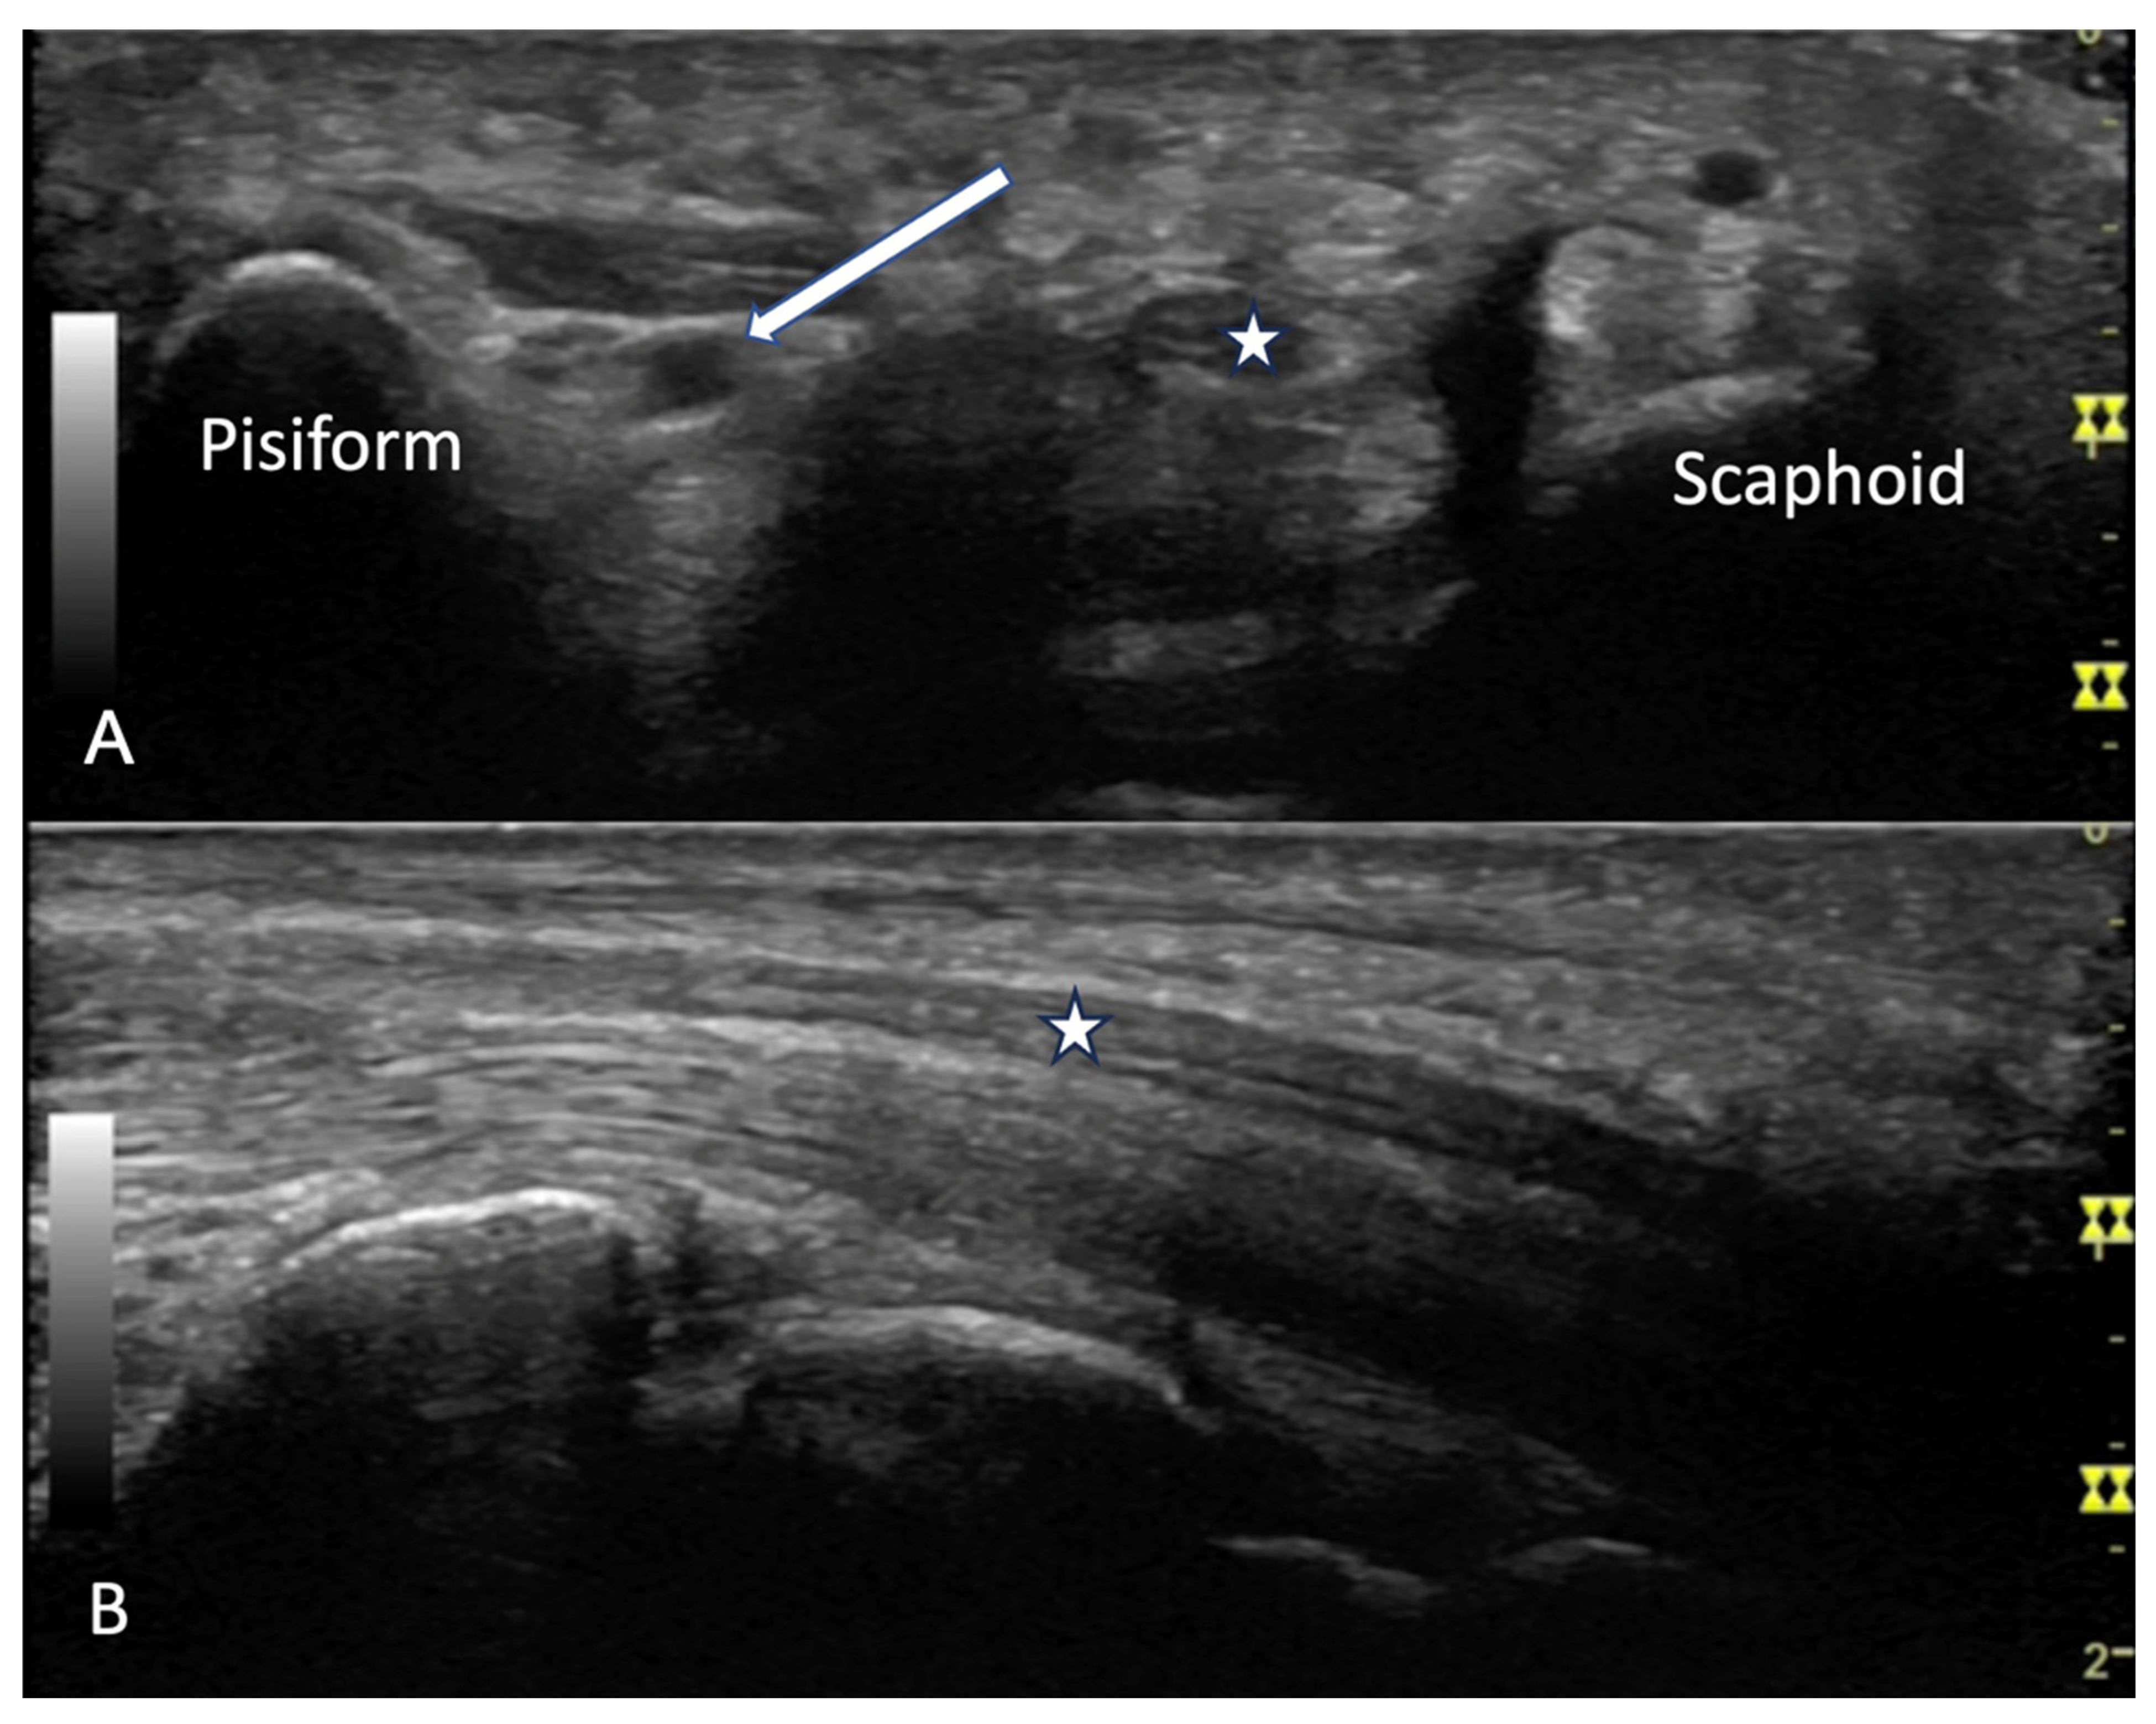

Carpal Tunnel Syndrome

4.2. Evaluation of the Wrist

4.2.2. Volar Aspect